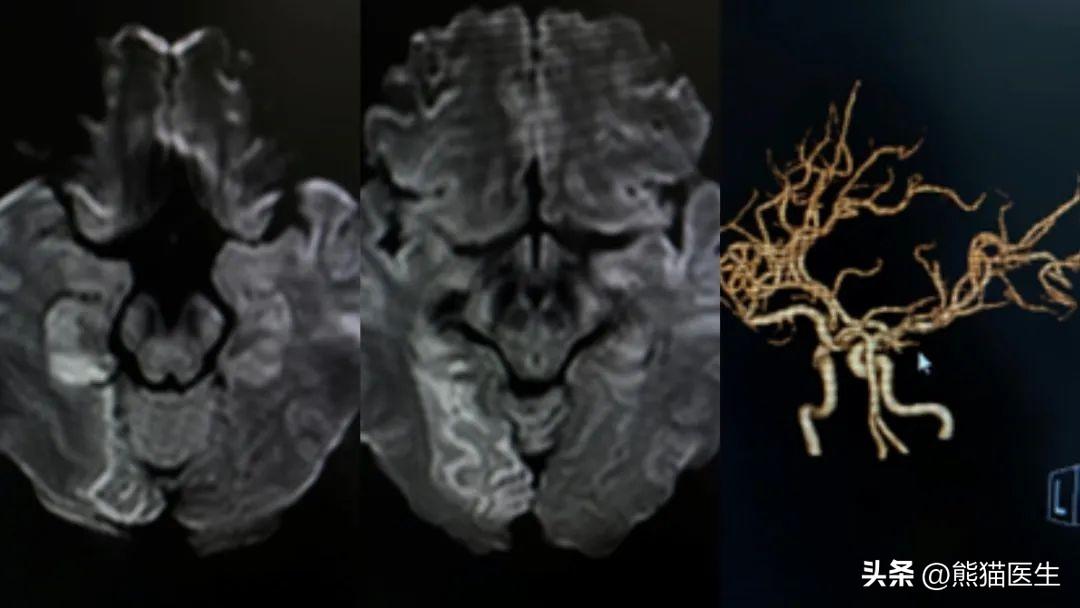

“明明只有32岁,怎么就会得‘脑梗’了?”在王女士后续住院期间全面的病史搜寻和检查中发现,病人有长期吸烟的嗜好,加上熬夜等不良的生活习惯,导致了大脑的动脉硬化,形成血管狭窄和血栓,最终形成了脑梗塞。通过核磁共振和增强CT证实王女士的脑梗塞面积还不小!

(病人脑部CT照片)